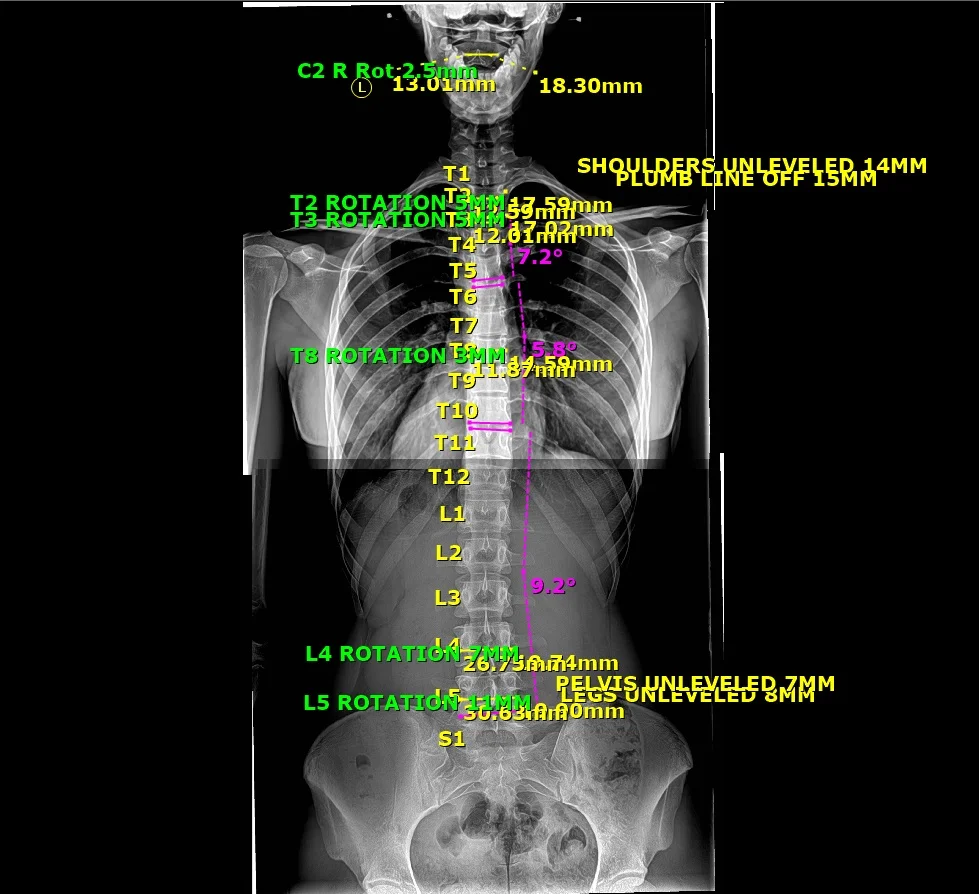

To remedy spine-related problems, assessments of X-ray images are essential to determine the spine and postural parameters. Chiropractic/manual therapy realignment of the structure of the spine can address a wide range of pain, muscle weakness, and functional impairments. Alternate methods to assess such spine problems are often indirect and do not reveal the root cause and could result in a significant misdiagnosis, leading to inappropriate treatment and harmful consequences for the patient. Radiography reveals the true condition and alignment of the spine; it eliminates guesswork. Contemporary approaches to spinal rehabilitation, guided by accurate imaging, have demonstrated superiority over primitive treatments. Unfortunately, there are well-meaning but misguided activists who advocate elimination or minimization of exposures in spine radiography. The radiation dose employed for a plain radiograph is very low, about 100 times below the threshold dose for harmful effects. Rather than increasing risk, such exposures would likely stimulate the patient’s own protection systems and result in beneficial health effects. Spine care guidelines need to be revised to reflect the potential benefits of modern treatments and the lack of health risks from low X-ray doses. This would encourage routine use of radiography in manual spine therapy, which differs from common pharmacologic pain relief practice.